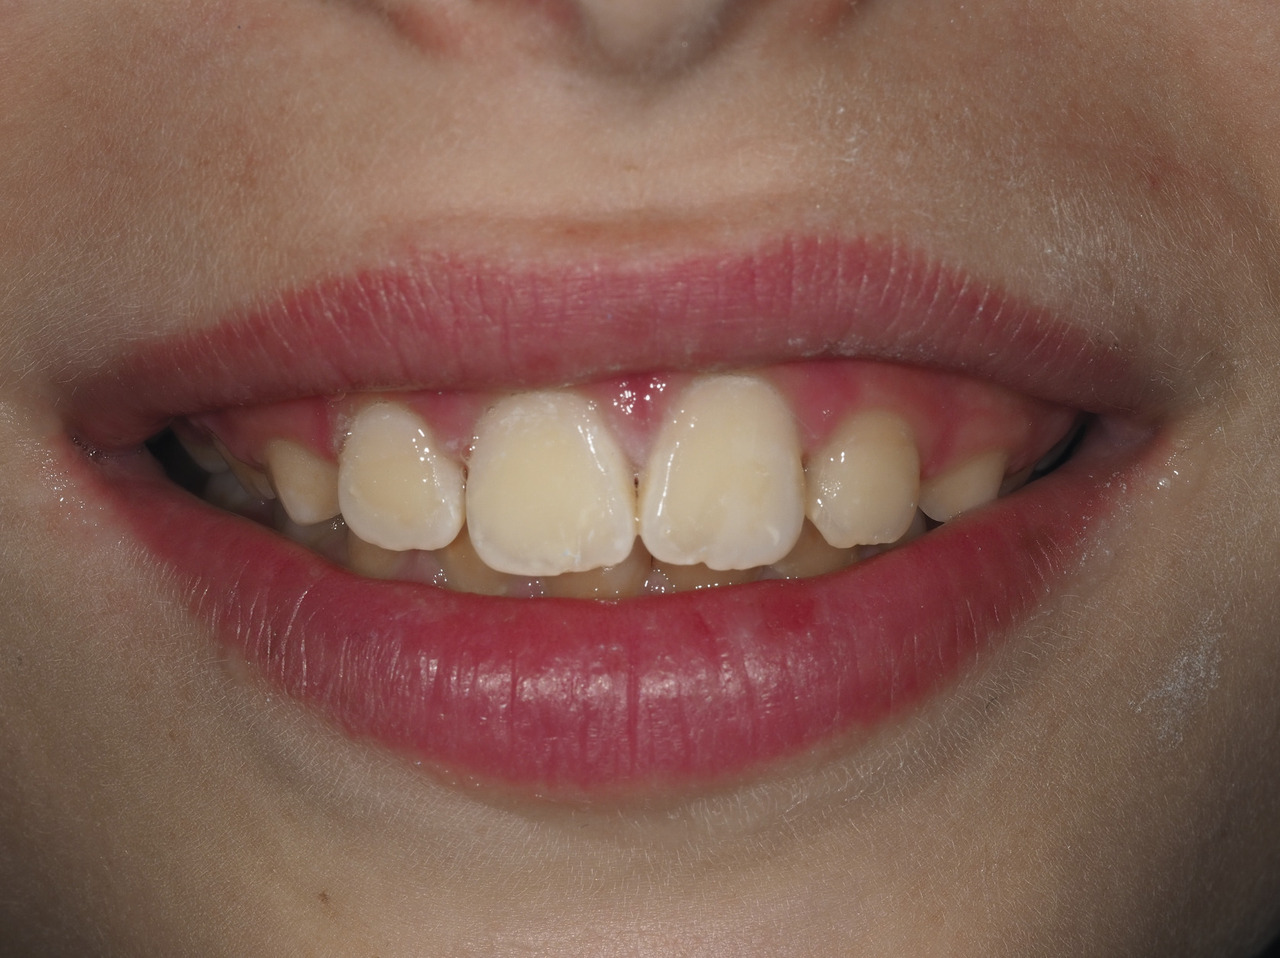

La présence d’opacités sur les incisives peut aussi avoir un impact esthétique qui altère la qualité de vie et l’estime de soi des patients.

Les dents antérieures ont rarement des pertes de substance ou des lésions carieuses ; la problématique réside dans l’aspect disgracieux des lésions (fig. 3 ). Pour la gestion de ces taches, des traitements plus ou moins invasifs peuvent être envisagés seulement pour des enfants avec une bonne hygiène bucco-dentaire et une coopération suffisante : micro-, macro-abrasion, ou infiltration résineuse.9 Ils sont utilisés seuls ou en combinaison et nécessitent parfois la réalisation d’une restauration collée en résine composite (fig. 4 ).

Les dents antérieures ont rarement des pertes de substance ou des lésions carieuses ; la problématique réside dans l’aspect disgracieux des lésions (